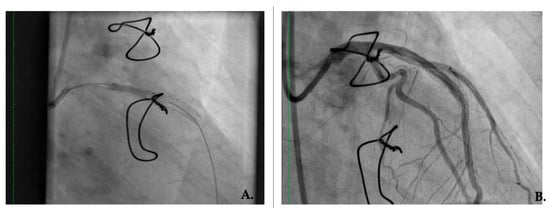

2. Case Presentation